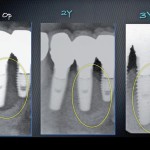

Predictable treatment of peri-implantitis

>Versione Italiana>

Atsuhiko Yamamoto, DDS, PhD

Lecturer, The Japan Institute for Advanced Dental Studies (JIADS), Osaka and Tokyo, Japan;

President, Perio-Implant Hospital AUTIS, Osaka, Japan

With the rapid advancement...

Trattamento predicibile di perimplantiti

>English Version>

A causa del grande...